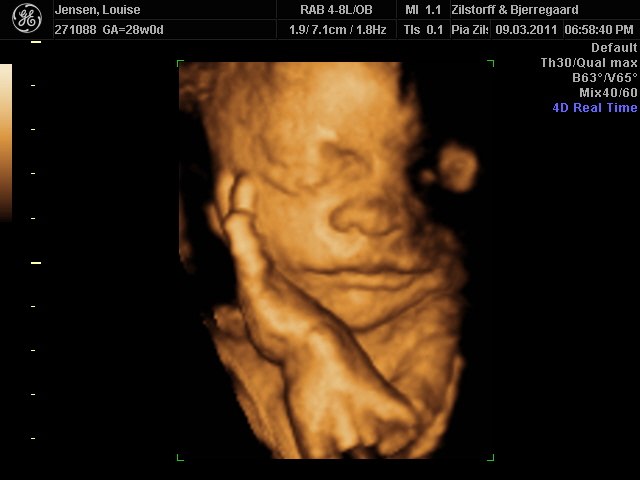

Jeg og kæresten var til 3D-scanning igår - sikke da en oplevelse  - det er da helt klart alle pengene værd ..

Hold da op en smækker lækker baby'boy der gemmer sig derinde i hulen, fy føj mor her fik tårere i øjne .. sikke da alt den kærliighed der væltede over mig .. suk suk

han ligner han far meget  - det er så vidunderligt hvad man dog kan se..

perfekt hjertelyd og vægten siger 1166 og er i uge 29 nu

Vedhæftede fotos (klik for at se i fuld størrelse)